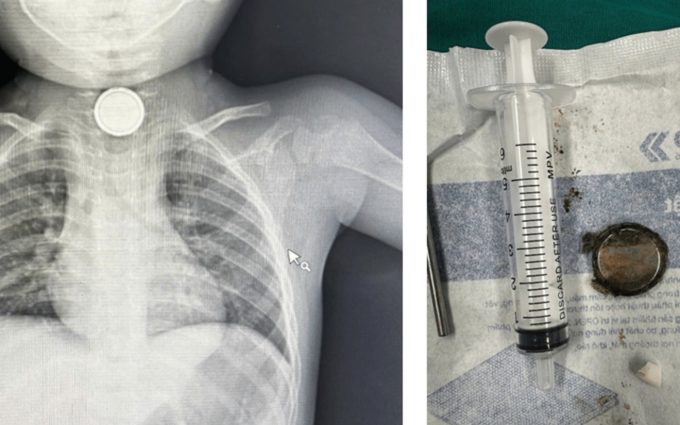

Ngày 23/2, BS.CK2 Nguyễn Minh Tiến, Phó giám đốc Bệnh viện Nhi đồng Thành phố, cho biết Xquang phổi ghi nhận dị vật hình tròn phần trên của ngực trẻ. Các bác sĩ chuyên khoa tai mũi họng, tiêu hóa nội soi đã gắp dị vật là cục pin tròn dẹp nằm ở 1/3 trên thực quản ra ngoài.

"Viên pin đã rỉ sét và viêm loét hoại tử niêm mạc thực quản", bác sĩ nói. Bệnh nhi được đặt ống thông mũi - dạ dày để giữ thực quản không bị chít hẹp, đồng thời dùng kháng sinh, thuốc băng niêm mạc và giảm tiết dịch đường tiêu hóa.

Viên pin trong cơ thể của bé trên phim Xquang (bên trái) và sau khi lấy ra ngoài (bên phải). Ảnh: Bác sĩ cung cấp